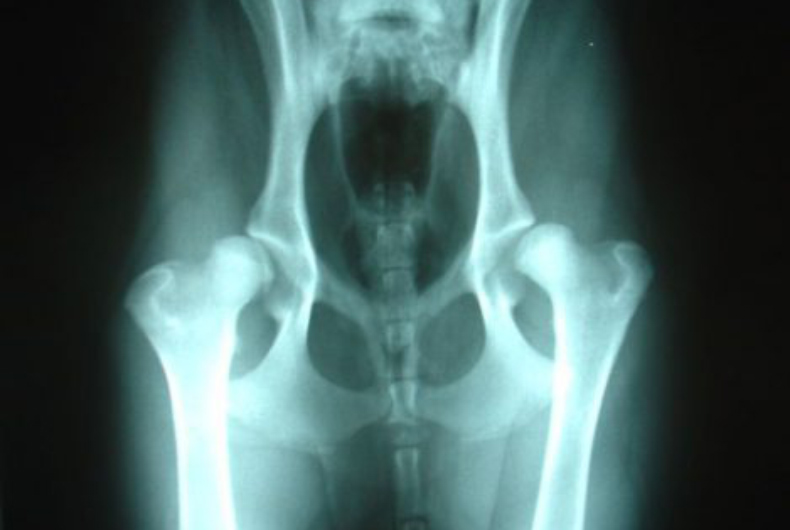

Chronic pain: Degenerative diseases like osteoarthritis and degenerative myelopathy, which affects the spinal cord, are more likely to arise in senior dogs and can be very painful if left untreated. Dog hip pain is the most common type, frequently caused by canine hip dysplasia or arthritis. Intervertebral disc disease (IVDD) occurs more often in certain dog breeds, like Dachshunds and Shih Tzus, commonly known as a “bulging” or herniated disc.

X-ray of a dog